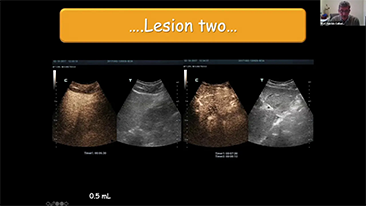

Hoe duidelijk is een lever te zien?

Bij focale leverlaesies, zoals hemangioom of leverkanker, speelt ultrasone contrastbeeldvorming een belangrijke rol. Ultrabrede niet-lineaire UWN+ contrastbeeldvormingstechnologie kan helpen bij het verkrijgen van een betere penetratie, een hogere contrast-weefselverhouding, met een lagere MI en een langere observatie van de perfusietijd.